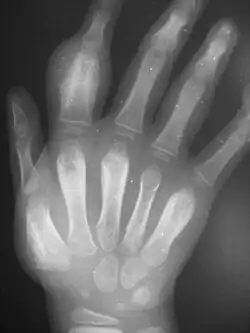

An irregularly-thickened first finger; proximal fingerbone is asymmetrically swollen

Dactylitis of secondary yaws due to periostitis

radiograph showing the same hand with thickened bones

Periostitis of secondary yaws may be visible on an X-ray, even if not otherwise visible[2]